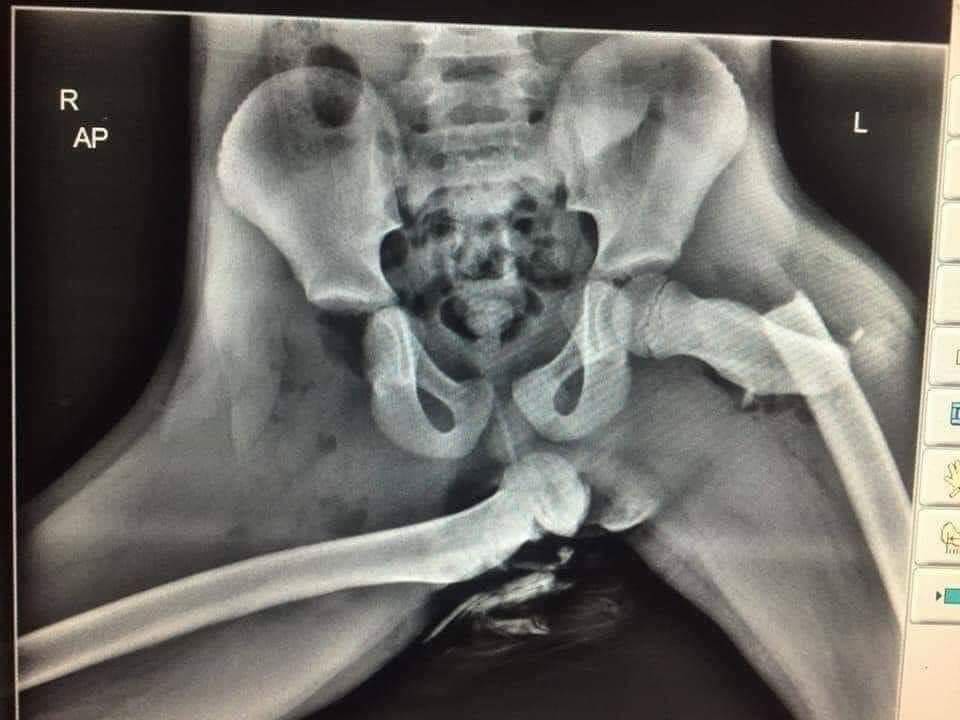

Internetom začal kolovať jeden nie celkom pekný obrázok. Údajne ide o RTG snímok spolujazdca po nehode, ktorý mal v nesprávny čas na nesprávnom mieste vyložené nohy na palubnej doske. A toto sa stalo z jeho panvou… Potrebuje to viac slov? Nemyslím si. Hodnovernosť obrázku bohužiaľ neviem overiť, každopádne aj sami si viete predstaviť, čo dokáže airbag napáchať.Pár z vás to určite už zažilo.